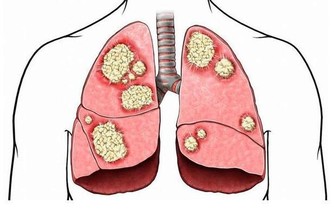

鼻咽癌晚期,殘酷的五個字,竟然和一名15歲少年聯系在了一起。由於發現晚,孩子也許只剩下5年時間…… 小明(化名)性格溫順,言語不多。父母在浙江打工,他跟著爺爺奶奶在老家安徽生活。3個月前,一直忙於農活的爺爺奶奶才注意到,孩子的脖子有些異常。 「脖子上就長了個包,有點硬,但是他身體都好好的, 我們也不知道呀。」現在回想起來,老人非常懊悔。由於缺乏醫學常識,小明脖子上的「包」越長越大,足足在脖子上突出了一個小拳頭大小,才告訴了父母。在當地醫院的檢查中,並沒有找到病因,後來父母把孩子接到杭州第一人民醫院,活檢證實是鼻咽癌。 「他這個年紀,怎麼會得癌症?」誰都不相信,尤其是小明的媽媽。 鼻咽癌在成人當中比較常見,兒童非常少見,但現在20、30歲的鼻咽癌患者在逐步增加,為什麼小明卻感染了呢? 影響因素一: 鼻咽癌的發病是多方面的原因,和EB病毒有關系,95%以上的成人都攜帶了這種病毒,它是傳染性單核細胞增多症的病原體,所以家長不要嘴對嘴的給孩子餵食物。 影響因素二: 鼻咽癌和生活習慣、外部環境都脫不了干係。喜歡吃醃漬的食物,比如鹹魚、臘腸、泡菜等,容易患上這種癌症。 【醃漬食品三大罪狀】 1.含有致癌物質——亞硝酸胺 醃漬食品在醃制過程中會產生亞硝胺前體物亞硝酸鹽。人的胃液pH值在1~3時,亞硝酸或硝酸鹽(需經細胞還原成亞硝酸鹽)可與細胞中的仲胺合成亞硝胺類化合物。這些物質有較強的致癌作用。 2.容易造成人體維生素C缺乏和結石 蔬菜在醃制過程中,維生素C被大量破壞。醃制後,維生素C的成分幾乎「全軍覆滅」。大量吃醃菜,人體維生素C缺乏。因此,適當吃點醃菜可以調節胃口,增加食慾,但若嗜食醃菜成癖,則是不可取的。如果長期食用,容易引起各種疾病。 另外,醃制的酸菜中含有較多的草酸和鈣,由於它酸度高,食用後不易在腸道內形成草酸鈣被排出體外,而會被大量吸收,草酸鈣就會結晶沉積在泌尿系統形成結石。 3.影響黏膜系統,對腸胃腎髒有害 由於食品在醃制過程中,需要大量放鹽,這會導致此類食物鈉鹽含量超標,造成常常進食醃制類食品者腎髒的負擔加重,發生高血壓的風險增高。 此外,高濃度的鹽分還會嚴重損害胃腸道黏膜,故常進食醃制類食品者,胃腸炎症和潰瘍的發病率較高。 如果一定要吃,也要在醃制15天後亞硝酸鹽下降至安全的劑量範圍內食用。 鼻咽癌早期有高達80%的治癒率,但是由於小明的情況比較特殊,家長反應慢,所以拖的時間較長,癌細胞已經轉移。「情況並不是特別樂觀。」李勇也表示惋惜,「治好了,可能也就5年時間吧。」 鼻咽癌的早期症狀 涕中帶血:早晨起床時,經常流鼻血,或是鼻涕呈淡粉色,有時帶血絲。 耳鳴,聽力減退,耳內閉塞感。頭痛:單側頑固性頭痛,偏頭痛多發生在顳頂部。頸部淋巴結腫大。鼻塞。 因為早期症狀不典型,多數被誤診為鼻炎,中耳炎,頸部淋巴結結核等。所以大家需要注意了,尤其是家長,如果一發現這些症狀,一定要及時就醫! 首頁還有更多熱門文章喔 網址傳送門 ww.happies.news